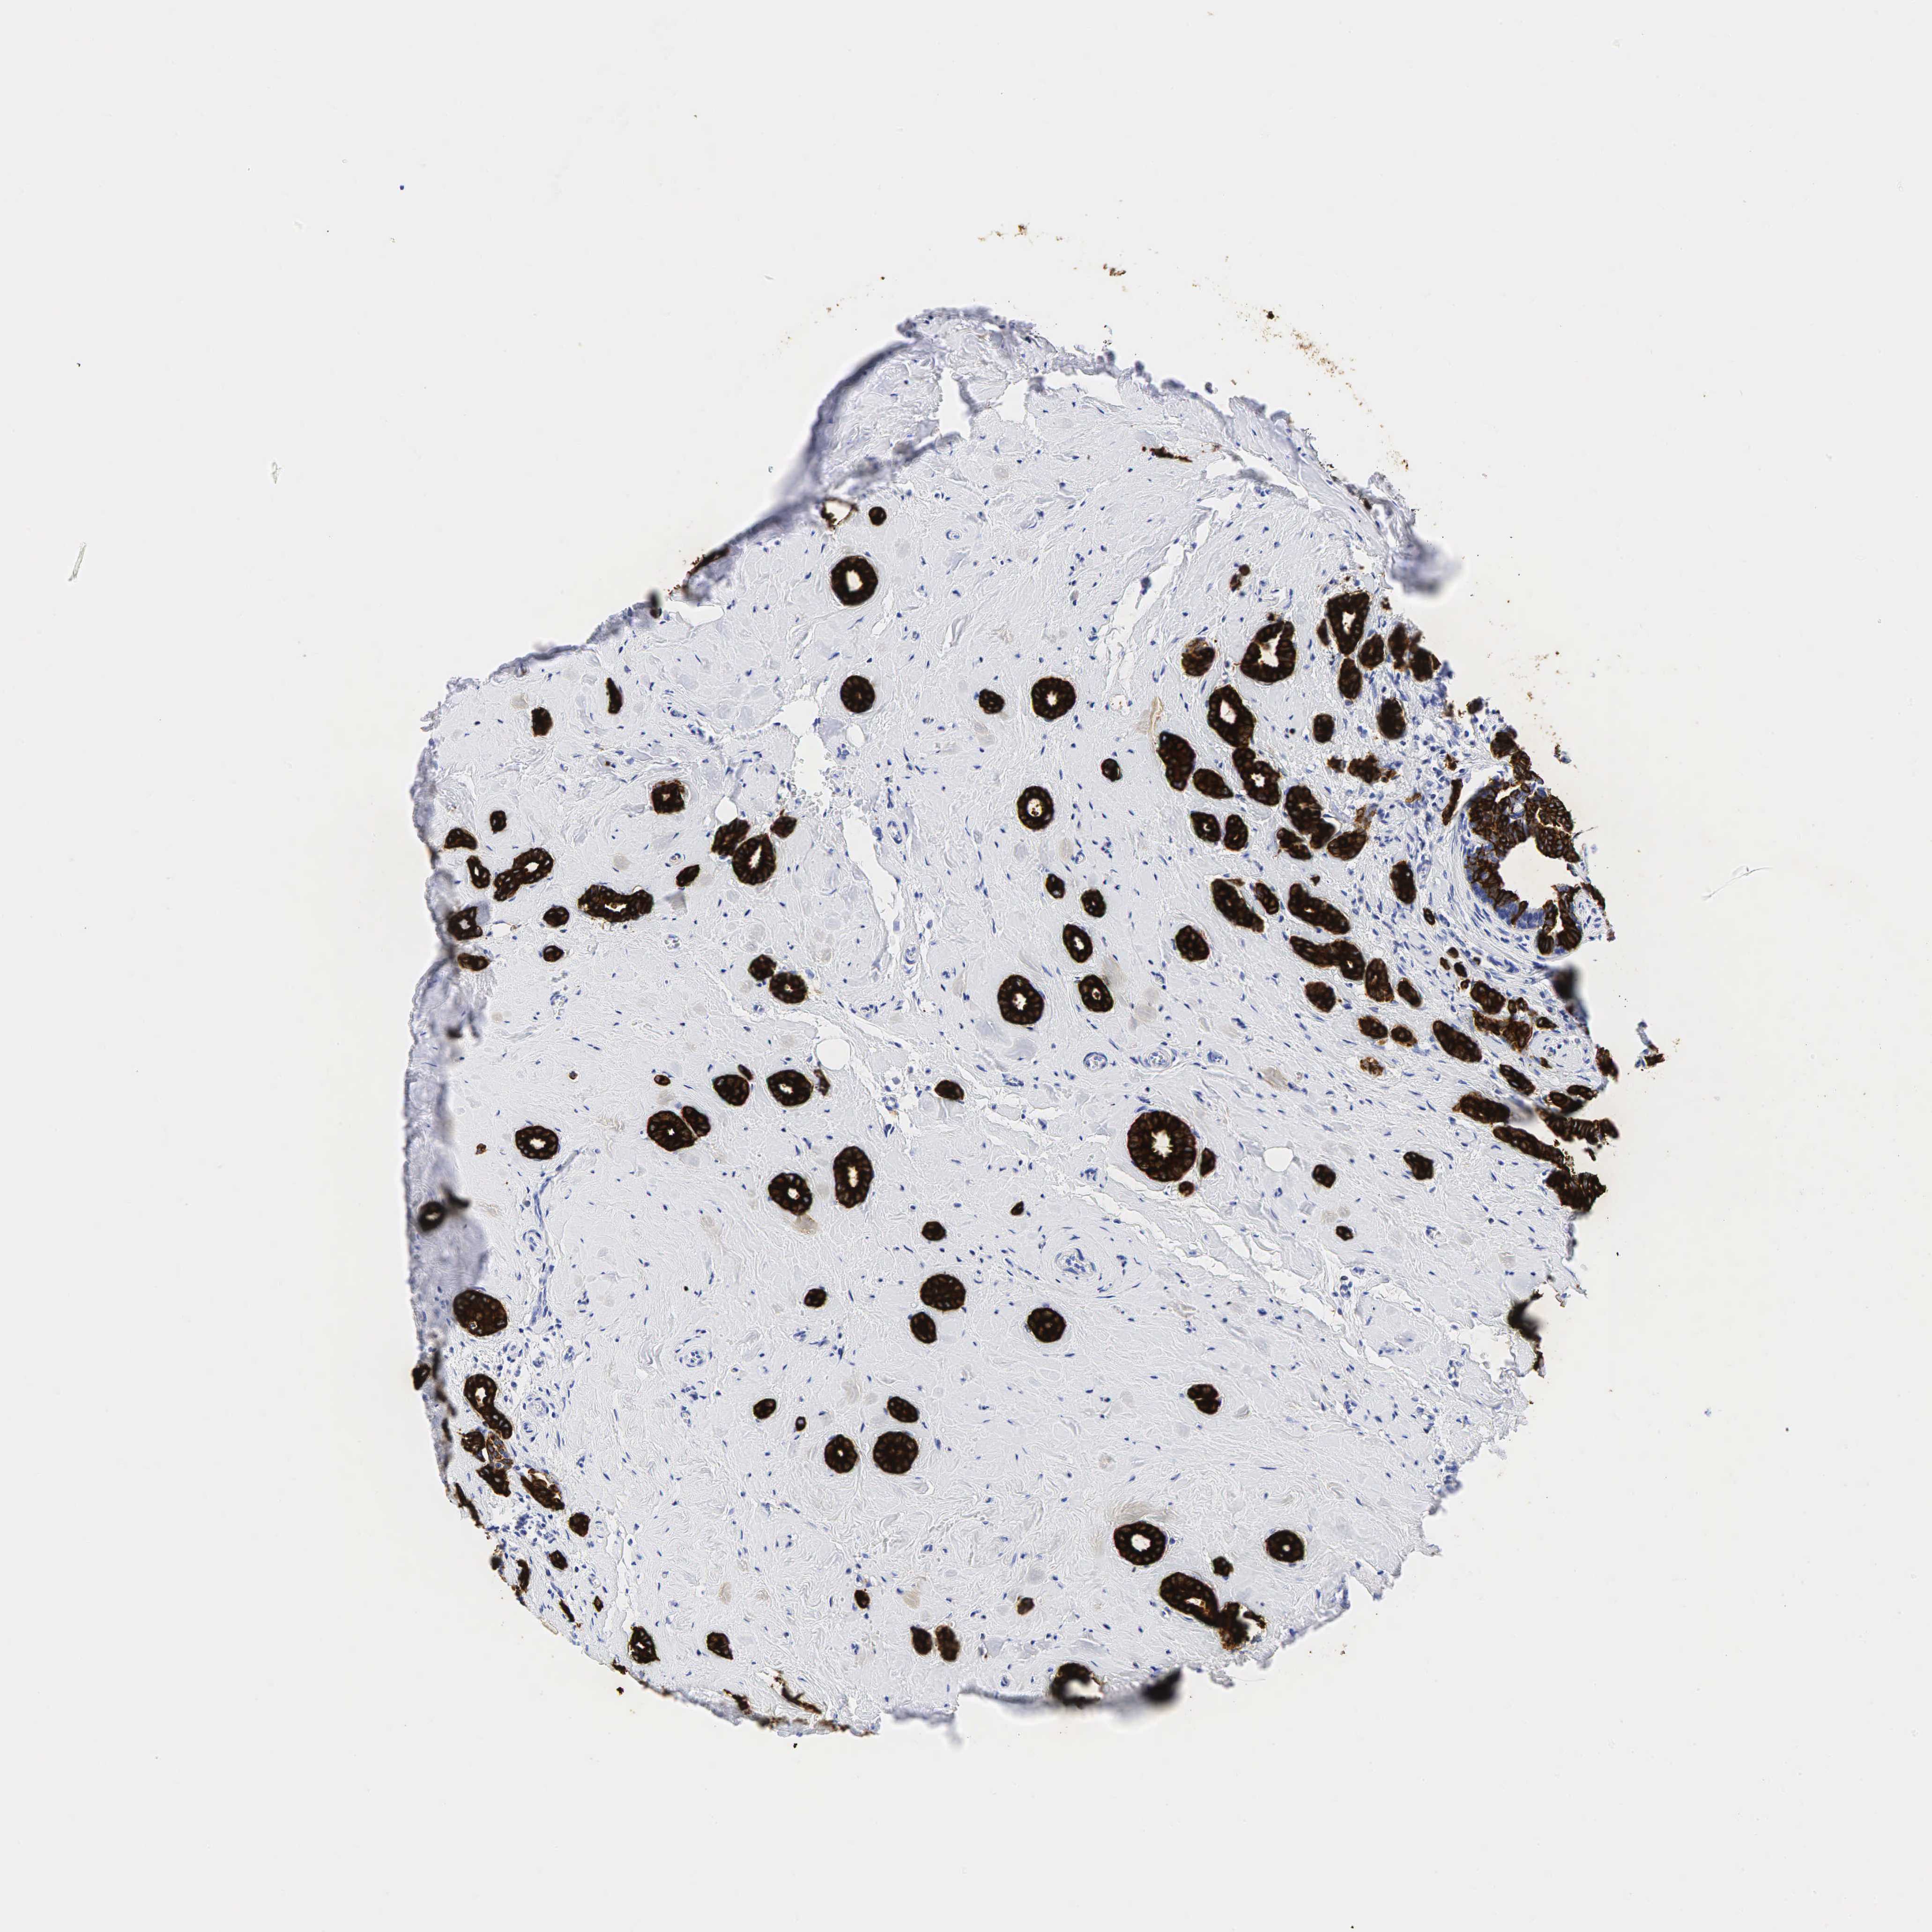

BRCA TCGA BRCA VALIDATION PROTEIN EXPRESSION